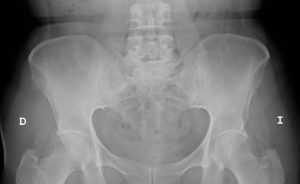

Rehabilitación prótesis de cadera

La rehabilitación de la prótesis de cadera comenzará antes de poner la misma, a esto se le llama rehabilitación prequirúrgica de prótesis de cadera, y constará de:

CADERA EN RESORTE

Se conoce como cadera en resorte a una afección caracterizada por chasquidos, en ocasiones audibles, que se producen en la articulación de la cadera, y es causada principalmente por el resalte del mús [...]